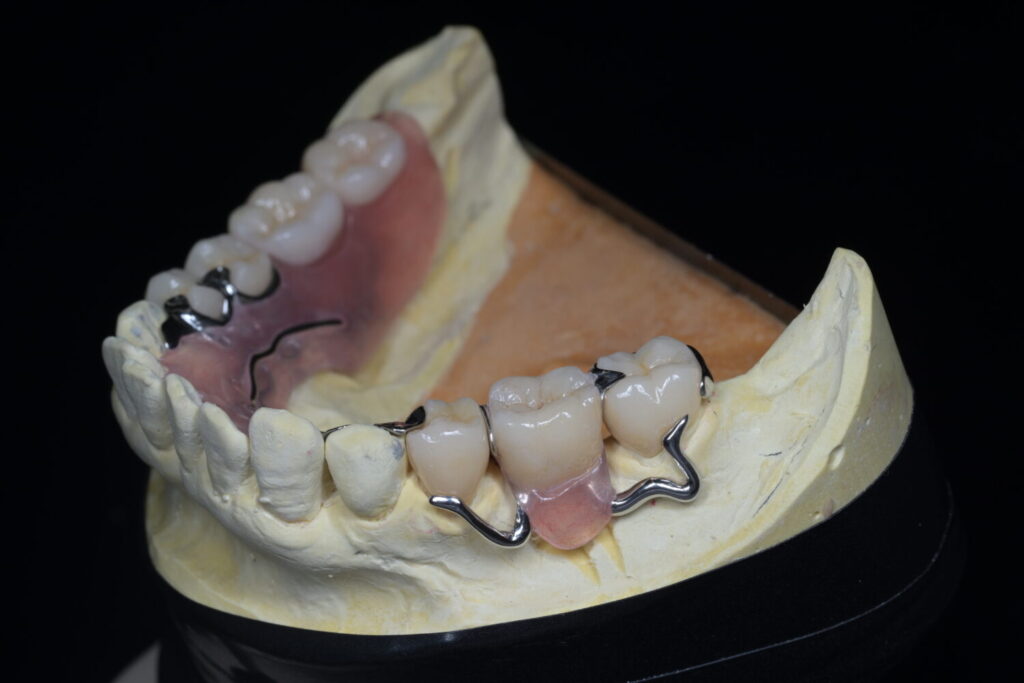

主人の場合、下顎は部分義歯タイプにする事になったので仮義歯を入れる際に、バネをかける歯に特殊な加工をしたサベイドクラウンという補綴物(被せ物)を作成しました。

入れ歯(部分床義歯)のバネ(クラスプ)が装着される歯(鉤歯)に施される、入れ歯の維持・安定を助ける特別な被せ物(クラウン)のことです。設計段階から、バネがかかる歯に対して、適切な掘り込みや面を事前に形成しておくことで、入れ歯がしっかり機能し、快適に装着できるようになります。

・入れ歯の安定性向上:部分床義歯のバネがしっかりと安定するための構造を付与しているので、義歯が外れたり動いたすることを防ぎ、快適に使用できる。

・バネをかけている歯の寿命がのびる:鉤歯に対して過剰な力がかかるのを防ぐことができます。

・長期的な快適性:着脱がスムーズになり、入れ歯を長期にわたって快適に使用できるようになります。